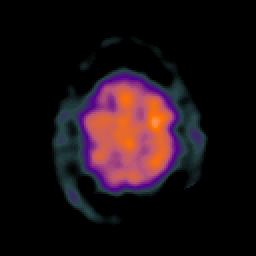

Glioma overlay -- Slice #24

[Home][Help][Clinical] Slice 24